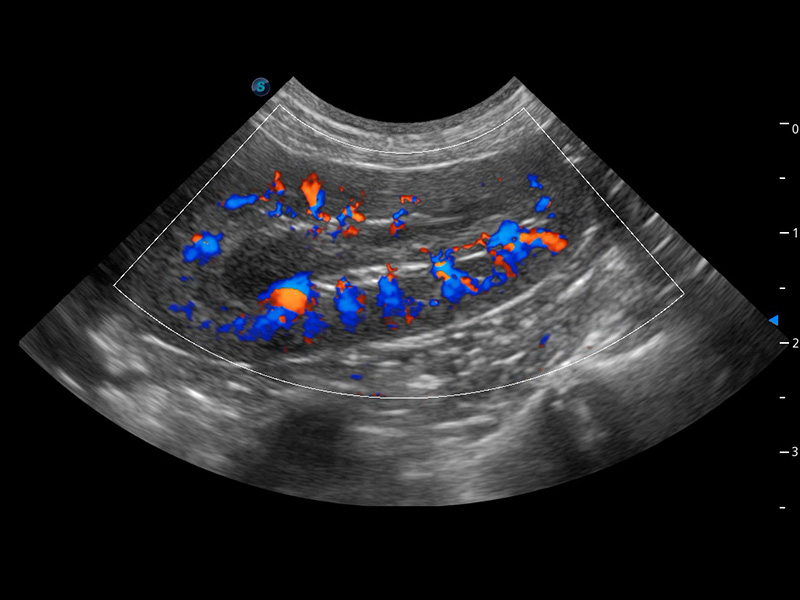

ProPet 60 作为一款高端台式动物超声设备,为动物医生的日常诊断提供了一系列贴合动物临床需求、解决临床实际问题的高级成像功能。凭借全系列高清探头,满足医生对腹部、心脏、生殖、浅表、肌骨等成像的所有需求,切实帮助您提升检查效率,提高诊断信心。

动物是人类最亲密的朋友和最值得信赖的伙伴。16877太阳集团也一直致力于探索动物专用的超声影像解决方案。 全新推出的ProPet系列,是16877太阳集团在动物超声影像智能化、专业化、精准化的一次跨越式革新。动物不能用言语来表述自己的不适,通过超声影像,ProPet系列搭建了动物医生与不同物种沟通的“桥梁”,为动物医生注入了“治愈之力”。